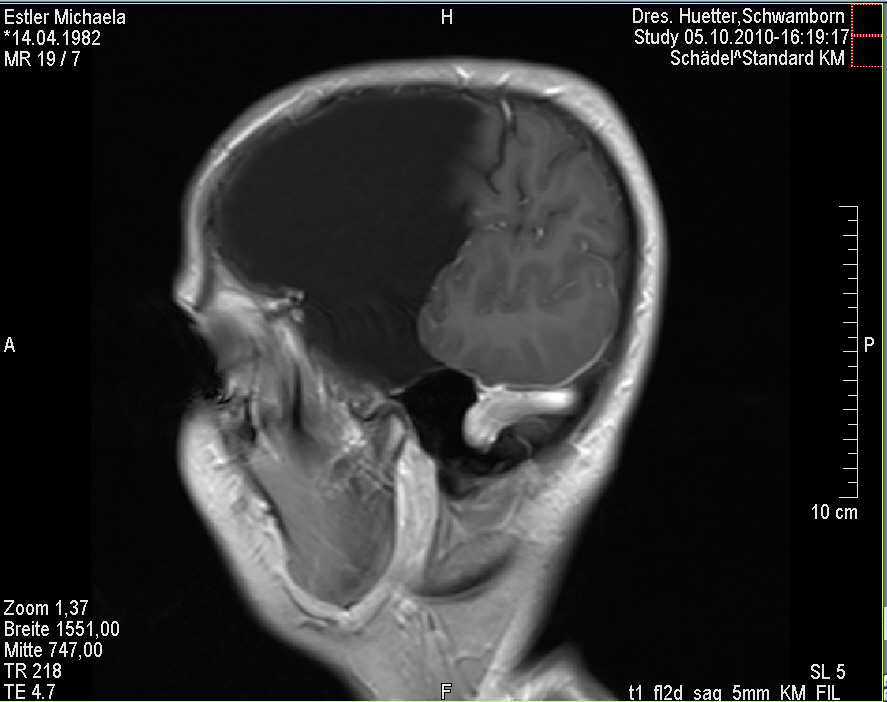

Ich stell euch hier noch eine kleine Galerie rein mit den neuesten Bildern. Ich denke es ist unübersehbar, dass das Ding gewachsen ist, außerdem mir meine komplette Hirnmittelline verschiebt und immer mehr Rücklagerung bekommt und Richtung Hirnsteuerungszentrum drückt. Meine häufiger auftretenden Stürze und Koordinationsprobleme werden also in naher Zukunft sicherlich nicht weniger werden und mein Doc und ich werden uns wohl auch zeitnah über eine weitere Klinik und eine mögliche weitere OP unterhalten müssen.

das ist bei mir ne Mischung aus Wasser und Gewebe. Das Thema ist, dass man die Flüssigkeit nicht einfach rausmachen kann, da sonst ein aktuer Unterdruck im Gehirn entsteht und das Gehirn reißen kann. Und dass ich dann nicht mehr all zu gut dabei aussehe denke ich erübrigt sich hier zu erwähnen….

Man hat in einer ersten OP damals schon mal einen halben Liter Flüssigkeit entzogen und dann gehofft, dass das gequetschte Gehirn sich wegen dem nachlassenden Gegendruck wieder weiter ausdehnt, aber das ist nicht passiert. Im Gegenzug hat die Zyste sich weiterhin wieder mit Wasser gefüllt und den entfernten halben Liter plus noch ein bisschen mehr wieder „nachgelegt“……